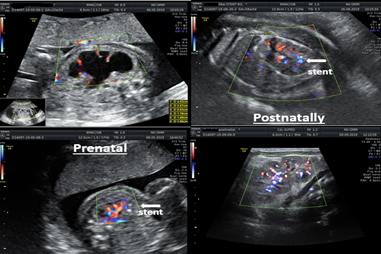

Figure 5,6 shows a case of bilateral nephroamniotic shunting surgery with the "SDE-MED" stent in case of PUV. Stent expulsions were not observed. Shunting surgery of the left fetal kidney was performed at 22 weeks of pregnancy, after 500 ml of amnioinfusion, and the shunting surgery of the right kidney was performed at 24 weeks of pregnancy. During the first procedure of intrauterine shunting, there was pronounced oligohydramnios, and the amniotic fluid index was equal to 4 cm, which required amnioinfusion in the volume of 500 ml. Indications for shunting surgery of the right kidney were grade III hydronephrosis, which did not stop after shunting surgery on the left kidney. Postnatally, the function of both kidneys was preserved. After surgical correction of the PUV disorder, the patient currently has pyelectasia in the left kidney.